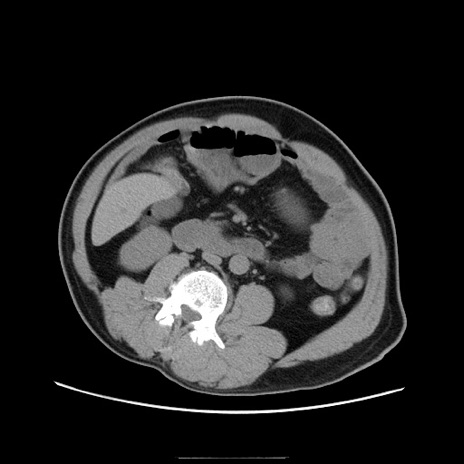

症例22(横断像)

【症例】50歳代男性

【主訴】腹痛

【現病歴】AVMからの被殻出血のため回復期リハ病棟入院中。 本日午後3時頃急に下腹部痛が出現した。

【既往歴】AVM、被殻出血、虫垂炎、高血圧

【身体所見】意識晴明、左半身不全麻痺、会話の理解は良好、36.5°C、腹部:膨隆、全体に板状硬、下腹部正中に圧痛点あり、反跳痛-、筋性防御不明、右下腹部にope scar

【データ】WBC 9400、CRP 0.06